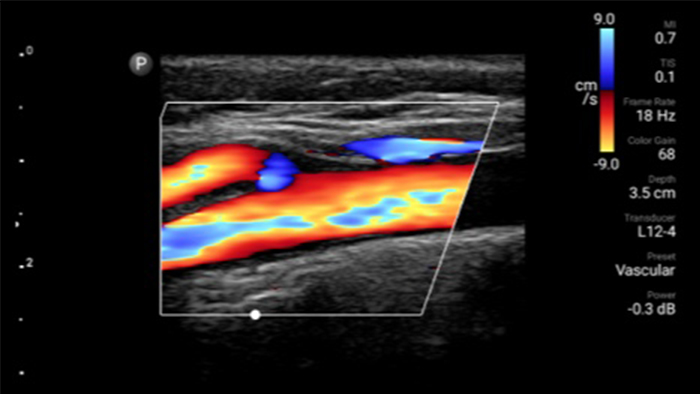

Exceptional ultrasound imaging

Lumify handheld ultrasound offers images that enhance diagnostic confidence.

See more when it counts

Lumify can help you make real-time decisions with more confidence, from assessment to recovery. Reveal the subtle details of an image, uncover enriched tissue definition with multiple angles and much more.